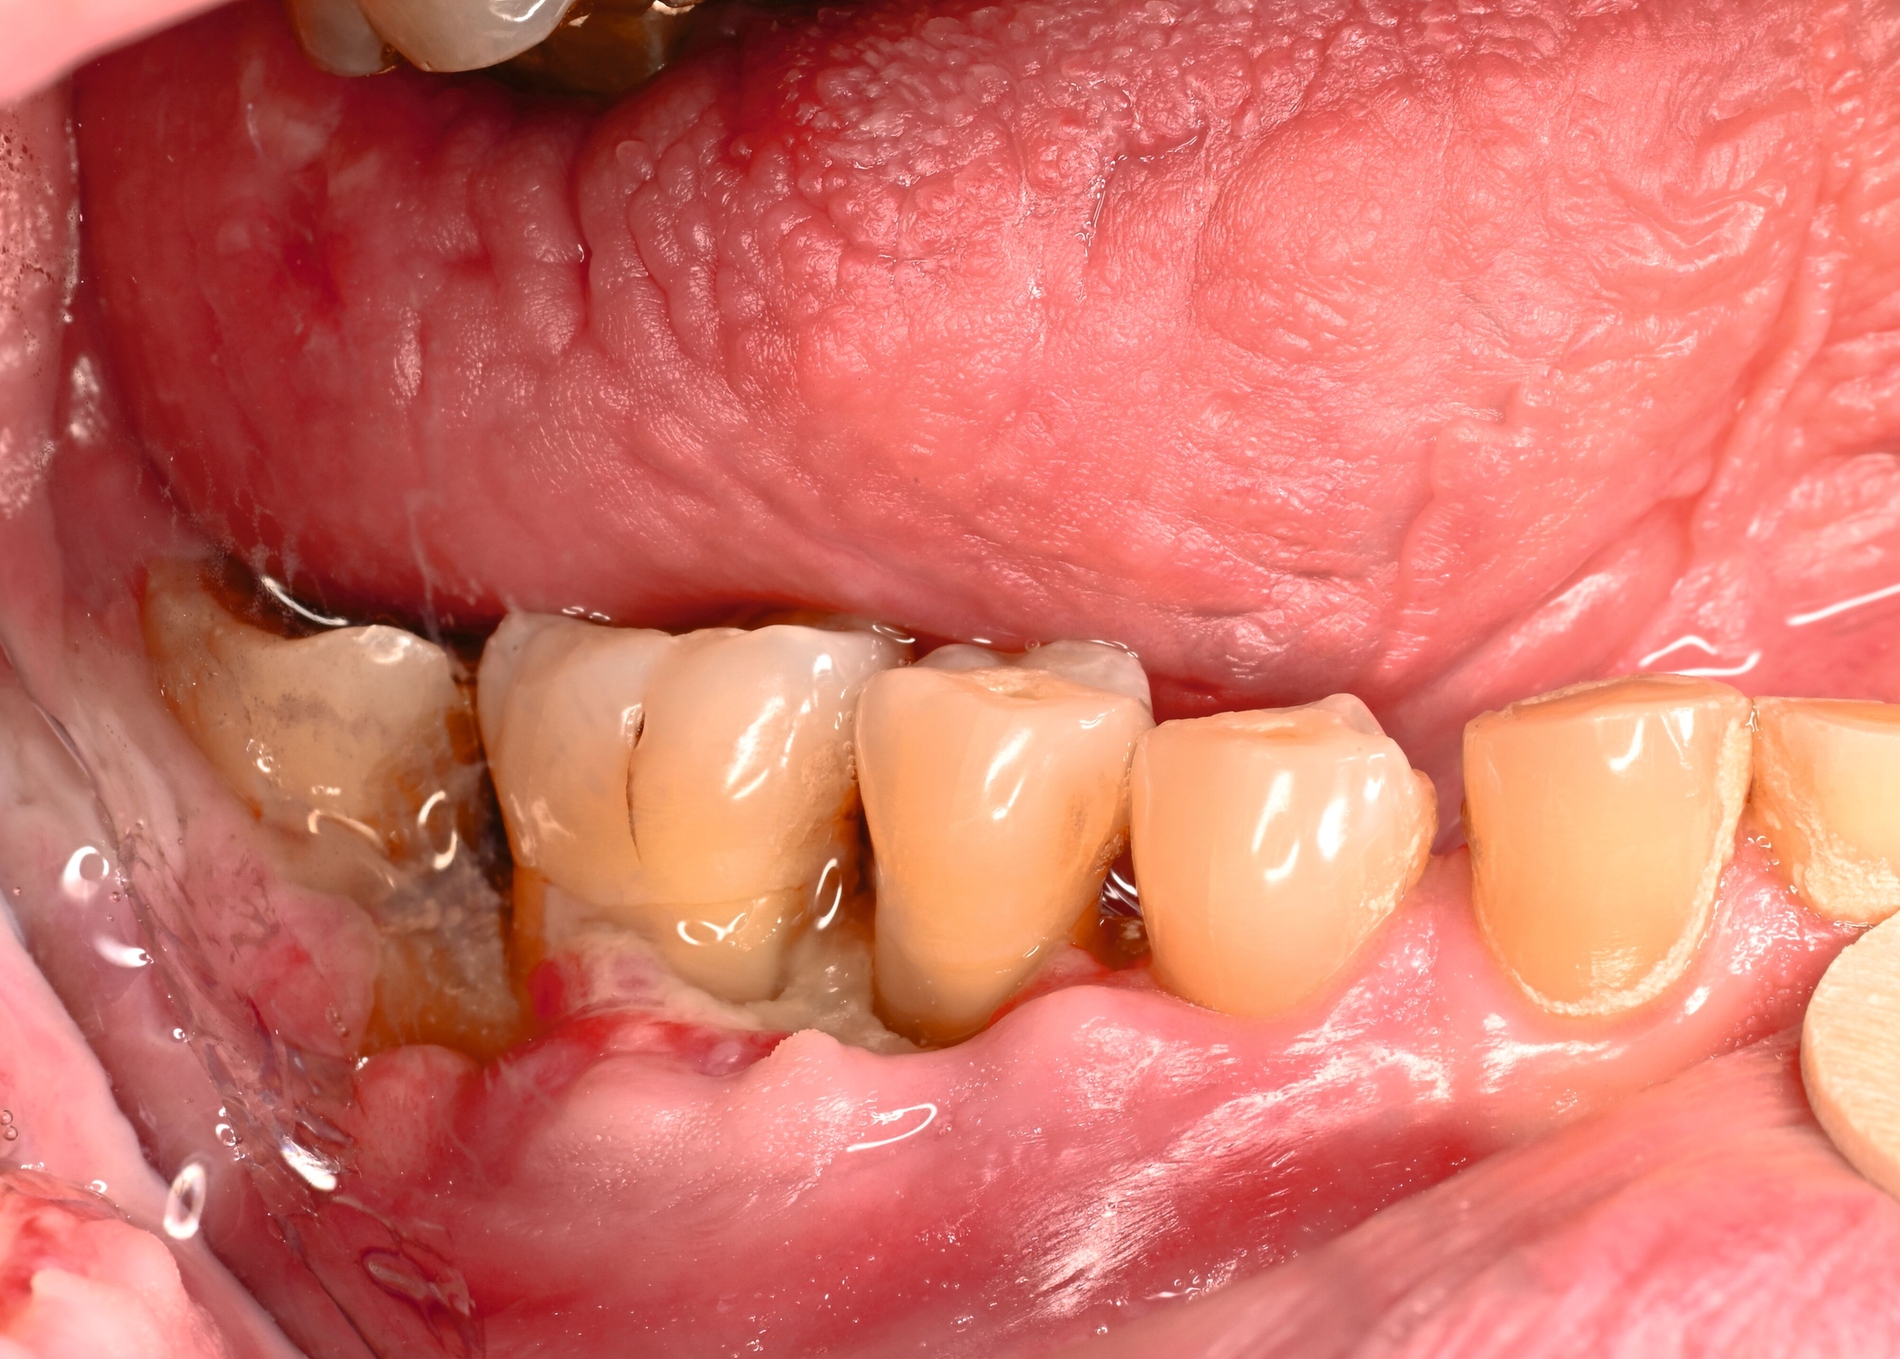

Der Patient stellte sich mit freiliegendem Knochen in Regio 43 bis 47 und mehreren gelockerten Zähnen vor. 45 und 46 waren devital. Als klinische Besonderheit fiel auf, dass sich innerhalb der Nekrosezone kleinflächige Weichgewebsareale darstellten, die in dieser Form bei klassischen Osteonekrosen üblicherweise nicht beobachtet werden. Eine klassische Vincent-Symptomatik bestand nicht. Drei Wochen zuvor war eine Herpes-Zoster-Infektion dermatologisch diagnostiziert und zunächst stationär behandelt worden. Der Patient erhielt eine intravenöse, antivirale Therapie, die bei Entlassung oralisiert wurde.

Zum Zeitpunkt der Erstvorstellung in der kieferchirurgischen Ambulanz zeigten sich keine klassischen Herpes-Zoster-Effloreszenzen im Gesicht. Eine antiresorptive Therapie oder Bestrahlung lag nicht vor, sodass eine Herpes-Zoster-assoziierte Osteonekrose im Sinne einer Ausschlussdiagnose festgestellt wurde. Anamnestisch bestand ein gut eingestellter Diabetes mellitus Typ 2 als potenziell immunkompromittierende Grunderkrankung. Die Knochenszintigrafie zeigte eine deutliche Stoffwechselsteigerung im betroffenen Bereich, vereinbar mit einer infizierten Osteonekrose.

In den publizierten Fallserien war der Unterkiefer häufiger betroffen als der Oberkiefer (Verhältnis etwa 3,5 zu 1). Der Krankheitsbeginn liegt meist zwischen der zweiten und der vierten Woche nach den Hauteffloreszenzen, kann aber auch verzögert auftreten [Mintz, 1992; Badjate, 2009]. Typisch ist ein einseitiger Verlauf entlang der betroffenen Nervenäste, auch mit spontaner Zahnexfoliation, freiliegendem Knochen und (manchmal) persistierender Neuralgie. Differenzialdiagnostisch müssen die MRONJ, die Osteoradionekrose und die bakterielle Osteomyelitis ausgeschlossen werden. Wenn diese Ursachen fehlen und eine zeitlich assoziierte Herpes-Zoster-Infektion besteht, ist die Diagnose einer HZ-assoziierten Osteonekrose naheliegend [Aghaloo, 2017].